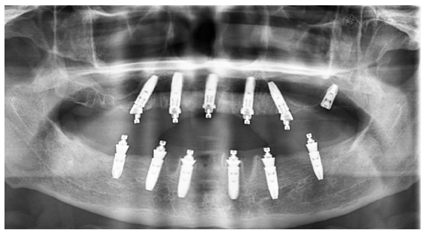

治疗过程:(1)术前准备:①藻酸盐取初印模,制作个性化托盘(图4);②用个性化托盘取硅橡胶终印模,灌制终模型;③制作光固化树脂

架;④排牙,制作放射导板(图6A);⑤试戴放射导板(图6B~D),拍摄两次CBCT(患者佩戴放射导板拍摄CBCT以及放射导板单独拍摄CBCT)。(2)方案设计:①将两次CBCT获取的DICOM数据导入种植设计软件重叠(图7),以修复为导向指导上下颌种植体位置摆放(图8、图9);②生成并打印手术导板(图10)。(3)利用手术导板和导板锁,翻制模型,制作临时修复体(图11)。(4)一期手术过程:铺巾消毒,局麻后拔除上下颌余留牙,搔刮拔牙窝内炎性肉芽组织,于34-36、44-46区牙槽嵴顶近远中向切开牙龈,翻瓣。就位并固定手术导板,于11、13、16、22、25、26、32、34、36、42、44、46定点,按术前设计方案植入NobelParallelTM ConicalConnection种植体。除26区种植体外,其余种植体初期稳定性均达到35N.cm以上,就位复合基台,戴入保护帽,修整牙龈黏膜,缝合牙龈(图12A~F)。术后拍摄全景片(图13)。次日复诊,取下保护帽,戴入预制的临时修复体,调合(图12G)。

治疗结果:术后3个月全景片显示种植体骨结合良好(图14)。26牙行二期手术,就位复合基台,戴入保护帽。两周后,取下临时修复体,制取上下颌硅橡胶印模,利用临时修复体交叉上